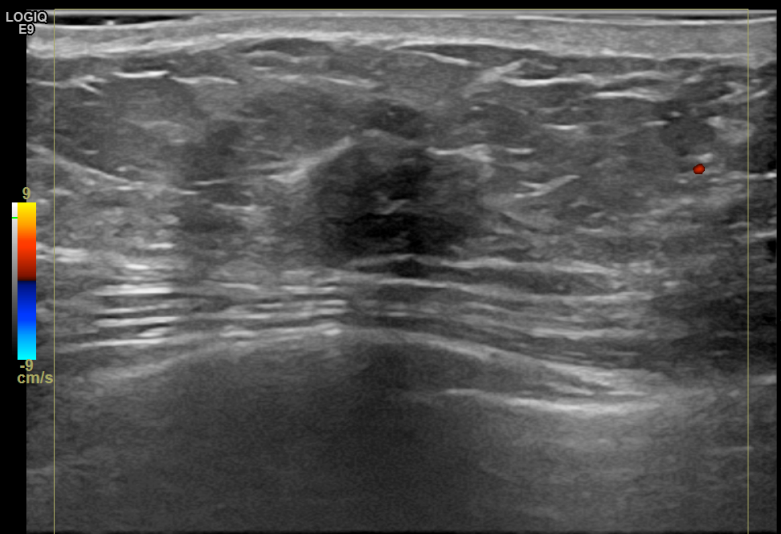

상기환자는 만져지는 멍울로 내원하신 50대후반 여성분으로 의심스러운 우측혹

조직검사 시행해 침윤성암으로 진단되었습니다